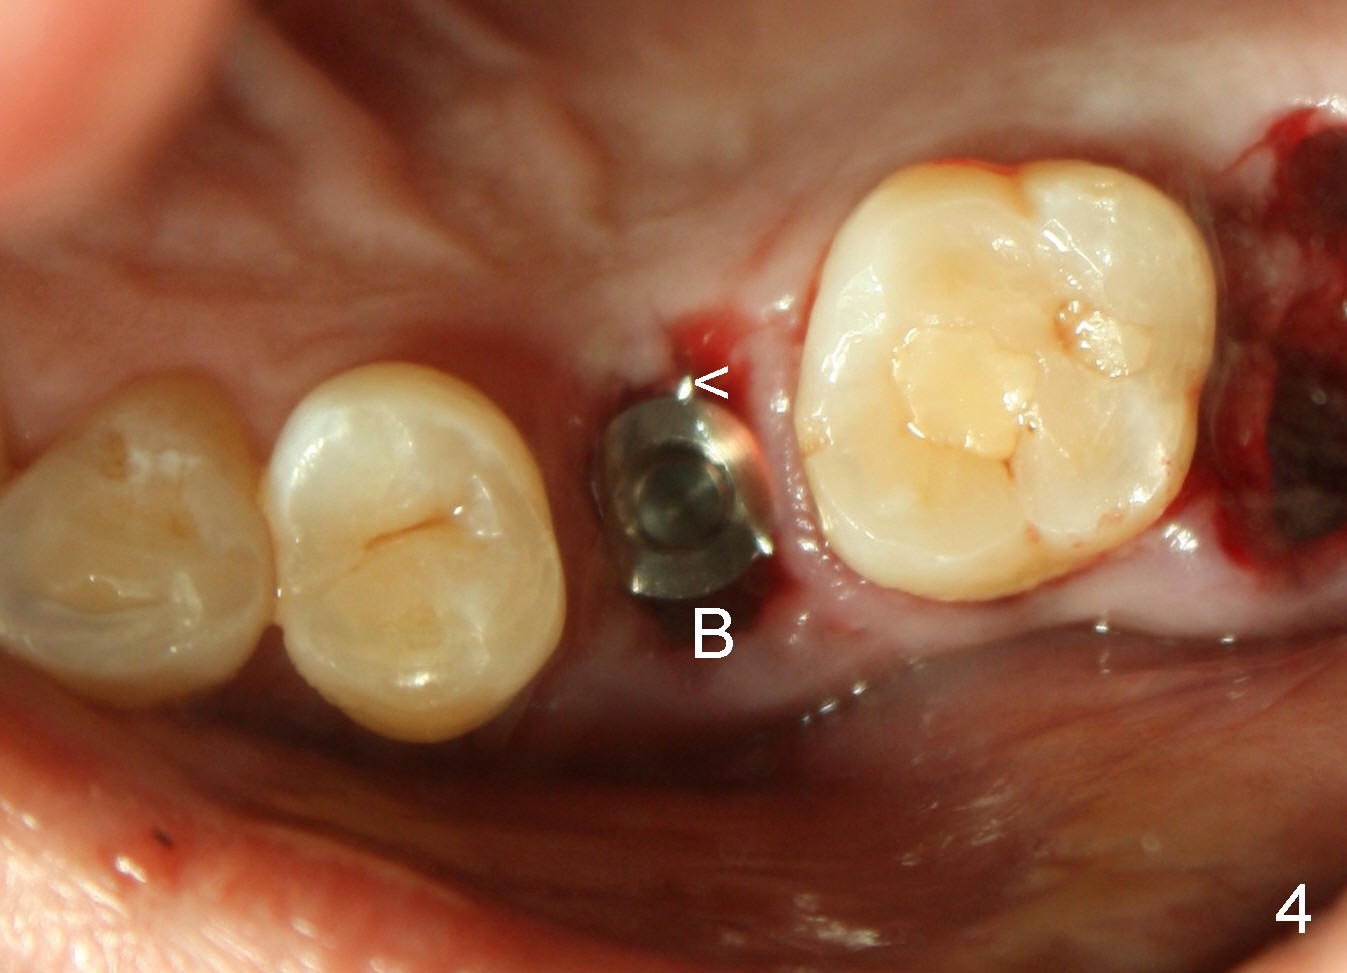

为了取得即刻植牙原发性稳定性(primary stability),一般需要在牙槽窝外钻洞至少四个毫米,形成新鲜创面,其实不必那么死板。四十三岁范女士牙齿不好,但是骨头特别结实,左上第二双尖牙断根不短(图一粉红色,大约十四毫米),根尖到上颌窦底板(红线)和鼻腔底部(蓝线)估计好十几毫米,我们使用最长植牙二十毫米,但是并不需要那么长,我们准备十七毫米长植牙。

牙根拔除后,牙槽窝深度十六毫米(从牙龈缘算起),开始钻洞十七毫米深,一直用到钻头直径四点五毫米,然后用适当力量旋入五乘十七毫米tap(图二),后者与牙槽窝接触很紧,突然意识到即刻植牙后,牙龈会有所退缩,所以钻洞再深一毫米,最后旋入五乘十七毫米植牙(图三I),torque超过六十Ncm。原先第一双尖牙(图一黄线)比第二长些,术后植牙稍微比第一双尖牙长(图三箭头),总之在新骨头里钻洞不需要太多,在这个病例里,大约二个毫米。